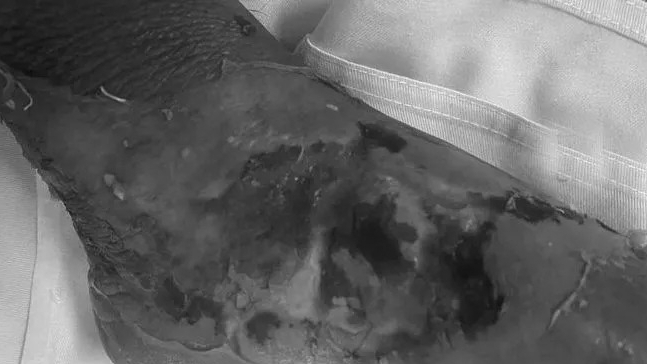

Ngay sau đó, ngày 16-17/9, Bệnh viện đa khoa tỉnh Tuyên Quang liên tục tiếp nhận thêm 02 trường hợp bệnh nhi: Nguyễn Bảo T (8 tuổi), trú tại Công Đa – Yên Sơn và Lý Thị H (5 tuổi), trú tại Phúc Ninh, Yên Sơn bị bỏng nước sôi độ II và độ III, sau khi bị bỏng, gia đình cũng đã đi lấy thuốc nam về đắp cho trẻ. Sau 1 ngày đắp thuốc không đỡ, thấy vị trí bỏng sưng, tấy đỏ, gia đình mới đưa trẻ đến Bệnh viện để khám bệnh. Hiện hai bé đang được điều trị tích cực tại khoa Chấn thương Chỉnh hình.

| Hình ảnh bé gái 8 tuổi bị bỏng nước sôi được gia đình cho đắp lá trứo khi đến viện ( ảnh BSCC) |